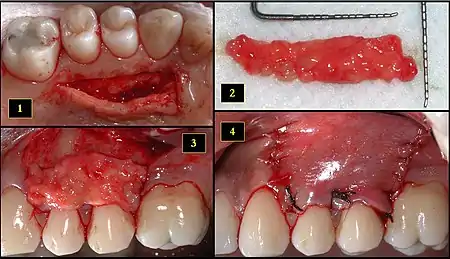

- Ipsilateral palatal mucosa serving as the donor site

- The retrieved connective tissue, approximately 25 × 6 mm in dimension

- Connective tissue placed at recipient site

- Recipient site flap coronally advanced and sutured to entirely cover the graft